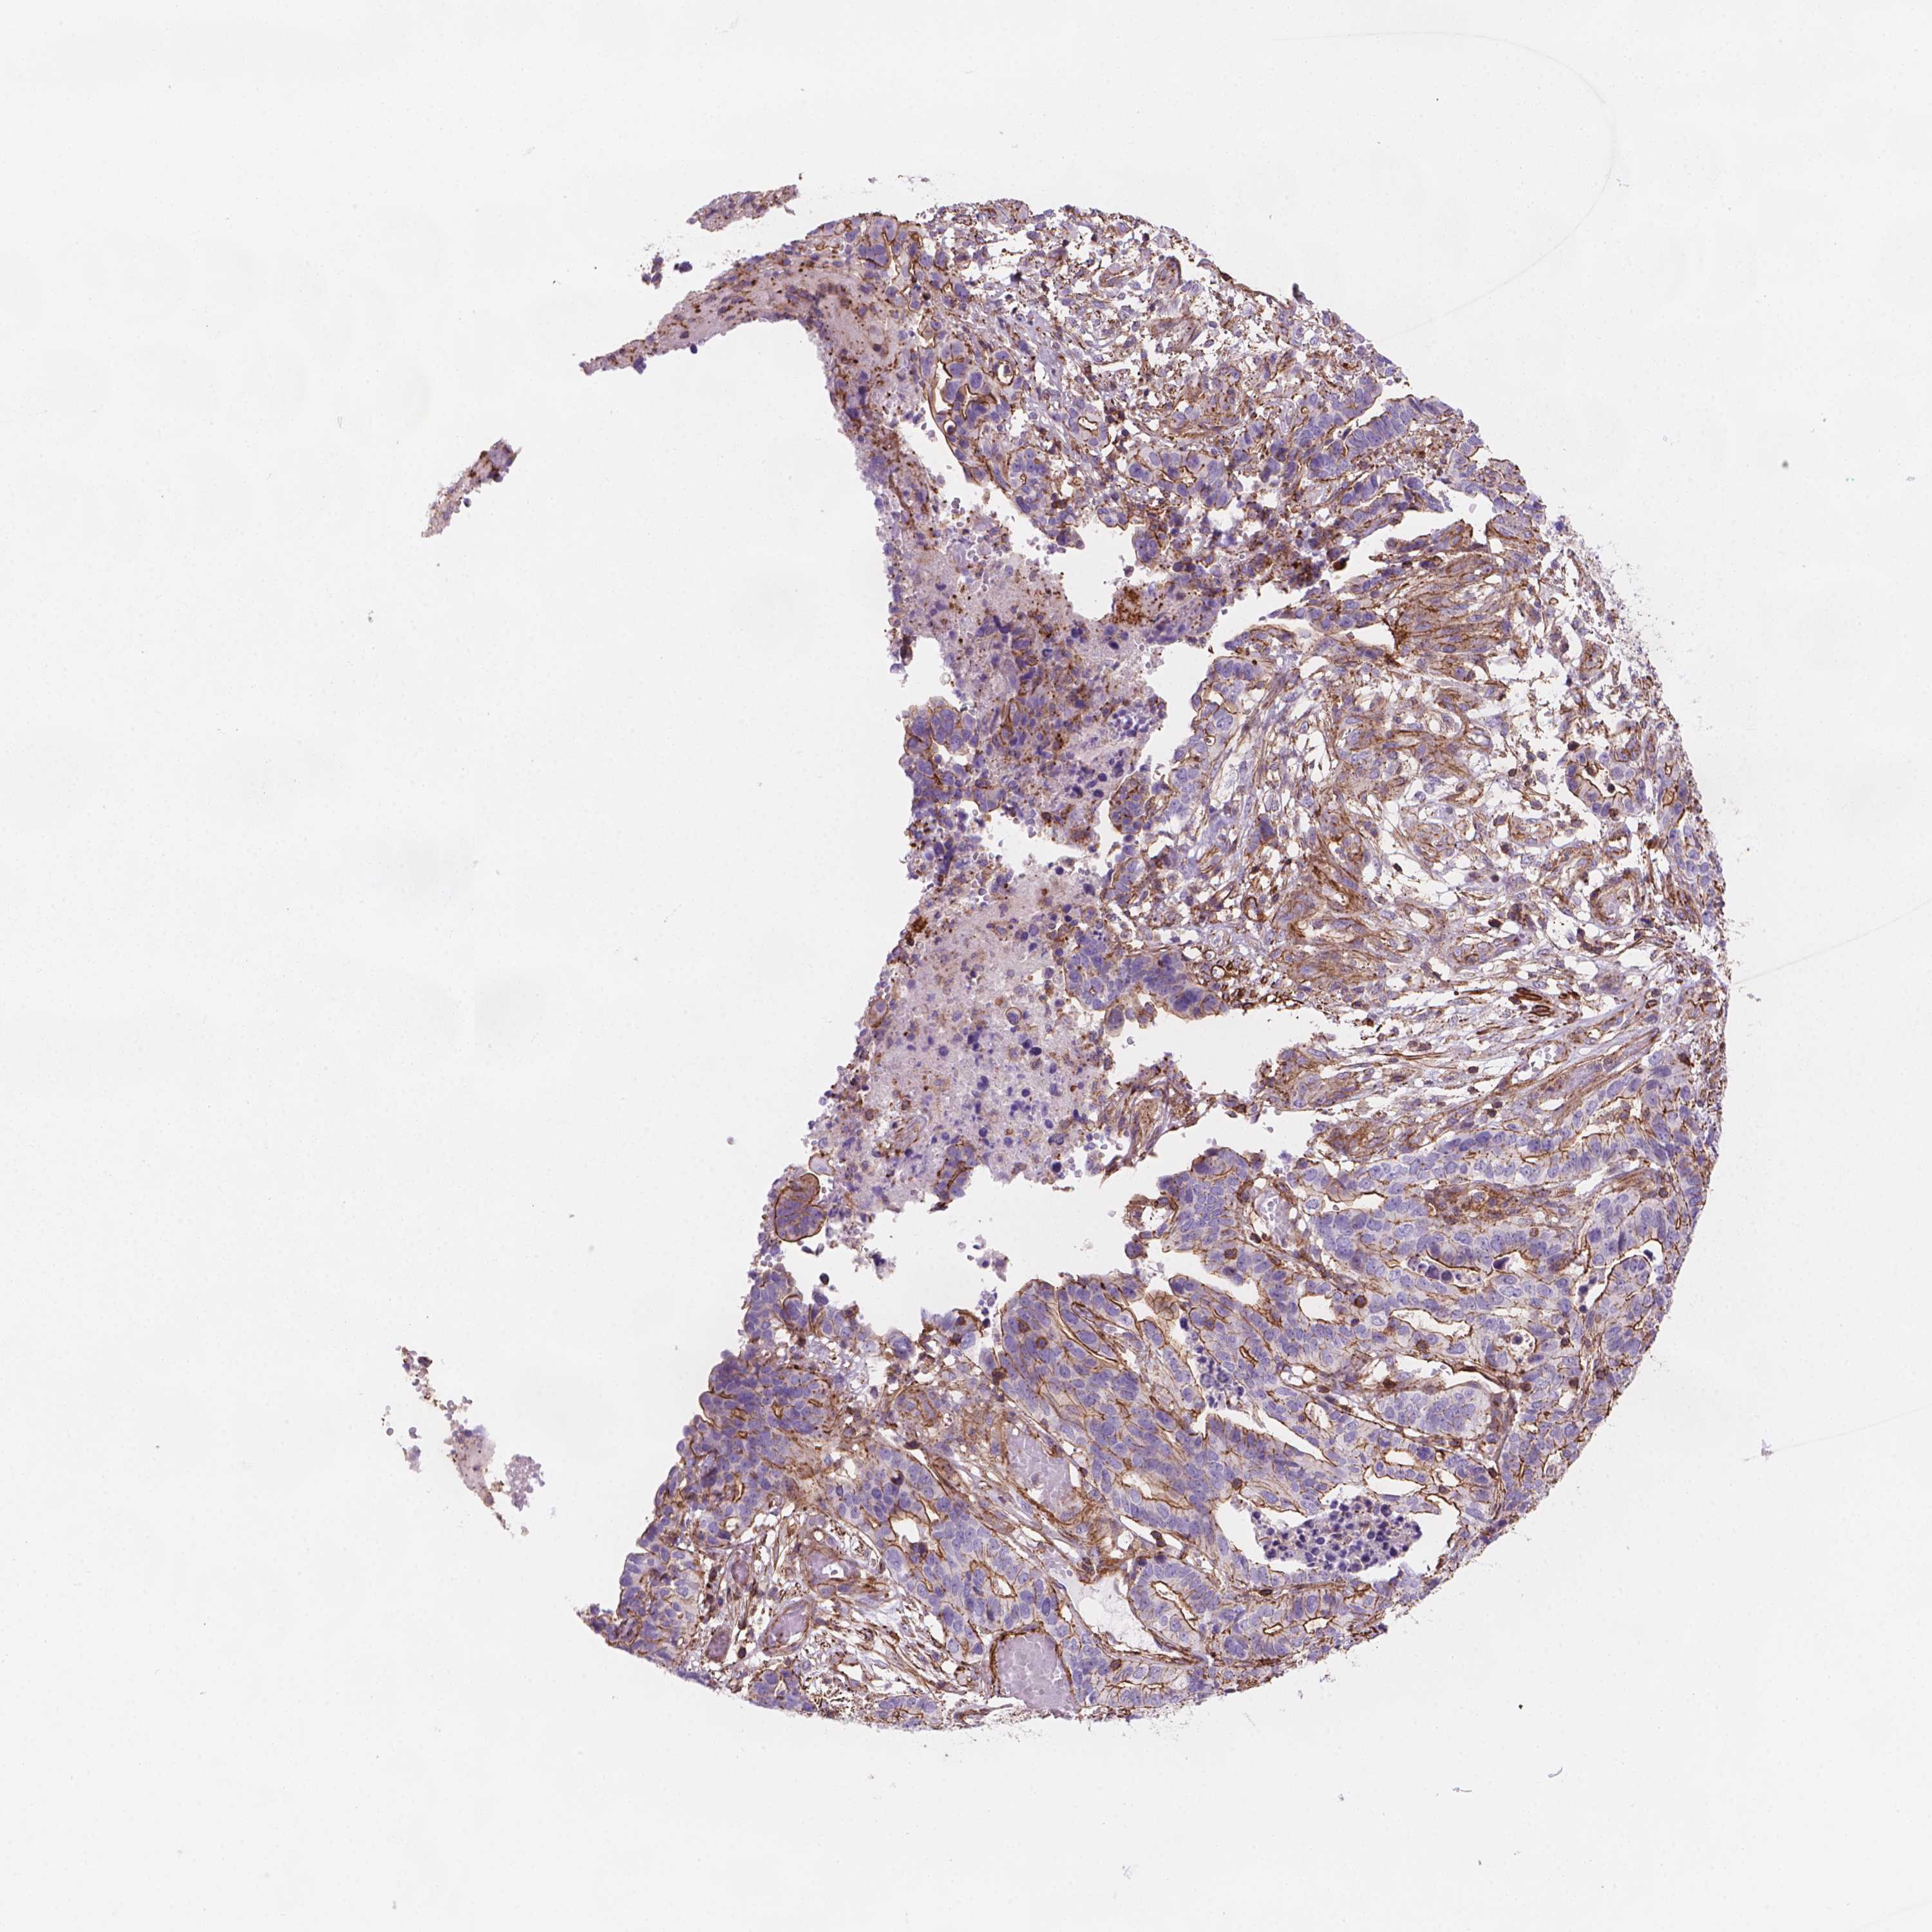

STOMACH CANCER - Protein expressioni

A mouse-over function shows sample information and annotation data. Click on an image to view it in a full screen mode. Samples can be filtered based on level of antibody staining by selecting one or several of the following categories: high, medium, low and not detected. The assay and annotation is described here.

Antibody stainingi

Antibody staining in the annotated cell types in the current human tissue is reported as not detected, low, medium, or high, based on conventional immunohistochemistry profiling in selected tissues. This score is based on the combination of the staining intensity and fraction of stained cells.

Each image is clickable and will lead to virtual microscopy that enables deeper exploration of all samples and also displays staining intensity scores, fraction scores and subcellular localization as well as patient and tissue information for each sample.

Antibody HPA066352

Staining

High

Medium

Low

Not detected

Intensity

Strong

Moderate

Weak

Negative

Quantity

>75%

75%-25%

<25%

None

Location

Nuclear

Cytoplasmic/membranous

Cytoplasmic/membranous,nuclear

Adenocarcinoma, NOS